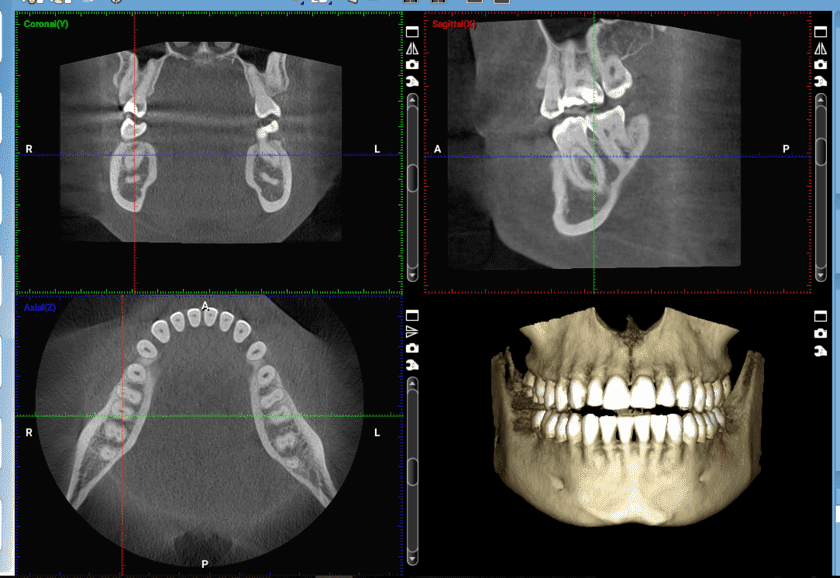

Chụp CT răng hay chụp cắt lớp vi tính nha khoa là kỹ thuật sử dụng tia X phản chiếu trên phim. Khi thực hiện, thiết bị chứa tia X đi qua vùng răng hàm mặt sẽ được hệ thống cảm biến xử lý bằng quy trình có sự hỗ trợ của máy tính để tạo ra hình ảnh.

Nhờ vậy, bác sĩ có thể dễ dàng quan sát và chẩn đoán một cách chính xác vấn đề răng miệng của bệnh nhân.

- Hình ảnh thu được có chất lượng cao và rõ nét

- Hình ảnh của các mô mềm có độ phân giải cao hơn so với khi chụp X-quang.

- Thích hợp để kiểm tra xương hàm do độ phân giải cao

Chụp CT cho hình ảnh có chất lượng cao và rõ nét

Dựa trên hình ảnh, họ có thể quan sát vị trí và sự phát triển của răng. Từ đó, đánh giá xem răng có mọc lệch hay không để nhổ một cách chính xác và dễ dàng.

Chụp CT giúp bác sĩ có thể quan sát, xác định cấu trúc của răng, xương hàm và các răng lân cận để tiến hành đặt trụ implant vào chính xác, đạt tính thẩm mỹ. Việc quan sát chiều rộng của xương giúp xác định xem có cần ghép xương hay không và lựa chọn trụ implant phù hợp.

Trước khi thực hiện niềng răng, bác sĩ cần xác định chính xác cấu trúc xương hàm, trục của răng, độ lệch và độ cứng của răng nên cần tiến hành chụp CT. Nó sẽ giúp quá trình thực hiện các thao tác chỉnh nha trở nên thuận tiện và chính xác hơn. Điều này đảm bảo cho khách hàng sự an toàn và hiệu quả tối đa.